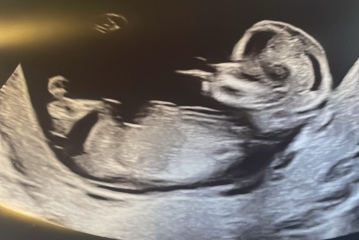

Nub? Is there no nub? Anyone got any guesses

Hello! I am expecting a 3rd (yikes!) and none of mine of my husbands family have girls so there is a lot of pressure. We are going to find out in a few weeks but just wanted to see what people thought? I’m happy with either but feeling the pressure to produce a girl 😬🫣. I have A LOT of photos. Asked for 2 but got 5 so I’ll post them all 😂